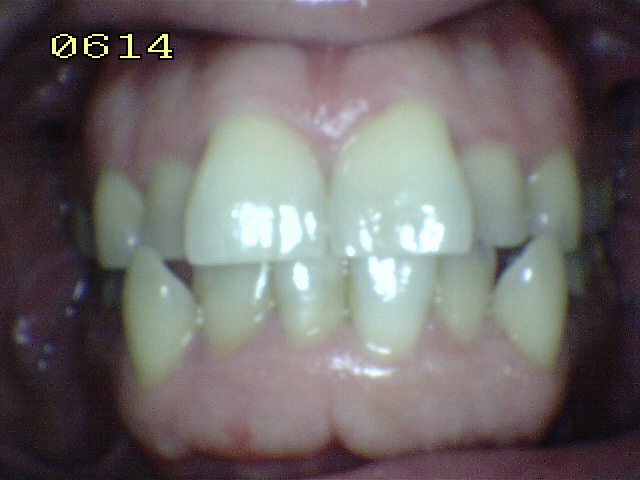

Clase III:

Ausencia de guía canina |

Observe el desgaste de las cúspides de canino y premolares

debidos al bruxismo excéntrico |